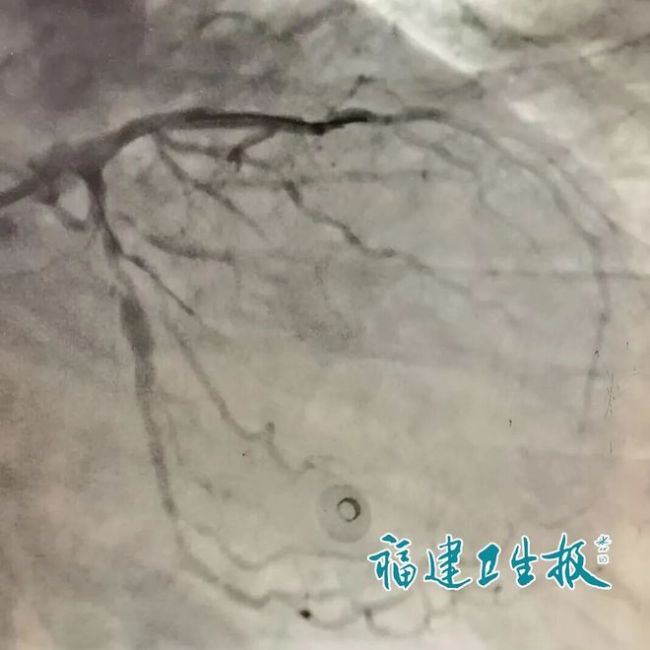

当天上午,来自贵州的叶大爷在武夷山旅游时突感胸骨后持续性闷痛,两小时未缓解,导游搀扶他到武夷山市立医院急诊科。首诊医生迅速为其完成心电图检查,结果显示V2至V4导联ST段抬高,呈典型的“墓碑样”改变,这是急性前壁心肌梗死的特征性表现,意味着心脏主要供血血管可能已被血栓完全堵塞,心肌正因大面积缺血而濒临坏死。